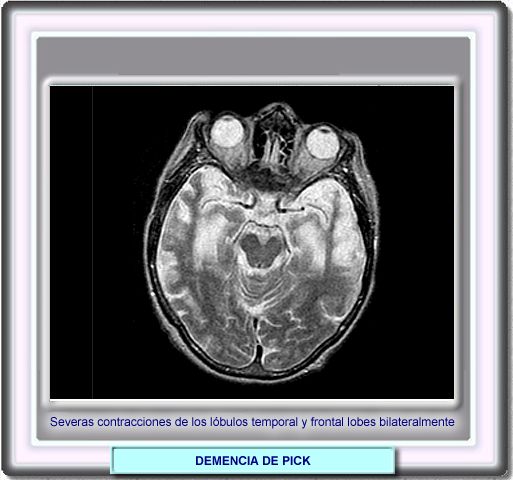

La atrofia cortical es fundamentalmente frontal y temporal y, a veces, marcadamente asimétrica y focal, con dilatación de las astas frontales y temporales. Ocasionalmente, se ponen de manifiesto por RM áreas focales de hiperseñal subcorticales en las secuencias ponderadas en T2 que reflejan fenómenos de gliosis.